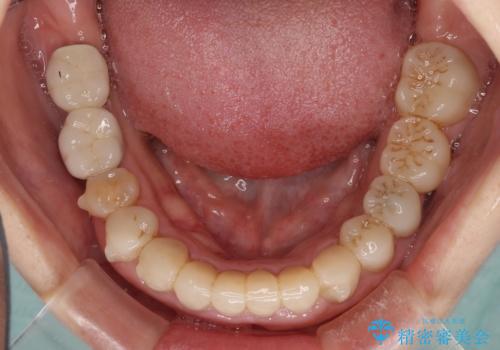

期間と費用はかかりましたが、気になっていた部分全てを改善でき、患者様には大変満足していただきました。